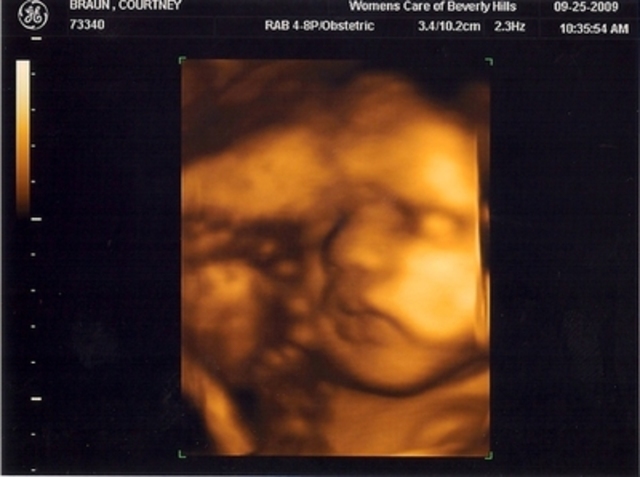

photo of thumb sucking